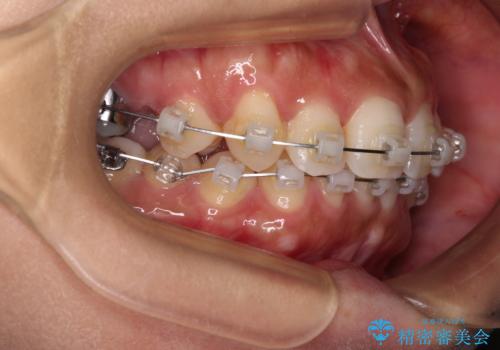

目立つ八重歯を改善 ワイヤー装置での抜歯矯正

- 目立つ八重歯を気にして来院された患者様です。

上顎小臼歯を抜歯するかどうか悩みましたが、八重歯の後方に失活歯があること、治療前に上顎正中が概ね人中に合っていることから、右上第二小臼歯を抜歯することとしました。

片側での抜歯であると、正中が抜歯した方向にずれていくため、左上の奥歯を遠心移動させる目的でアンカースクリューと補助装置を併用した上で、ワイヤー装置にて矯正治療を行うこととしました。

上顎の正中位置をほぼ保った状態で、綺麗に仕上げることができました。